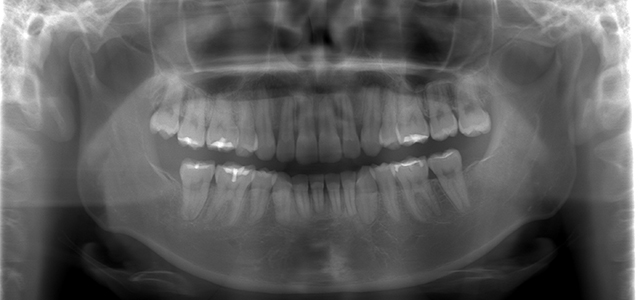

矯正前 パノラマX線

主訴 口元の突出感を治したい。ガミースマイルを治したい。

年齢 20代

治療法 上下顎マルチブラケット装置

抜歯の有無 上顎左右側第一小臼歯、下顎左右側第一小臼歯

治療期間 1年10ヶ月